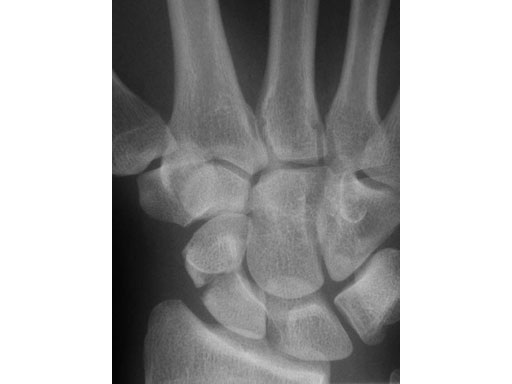

24-year-old male with an acute scaphoid wrist fracture treated by percutaneous fixation with a 3.0 mm headless compression screw under regional anesthesia.

Fig 1 Preoperative x-ray.

Case provided by Doug Campbell, West Yorkshire, GB